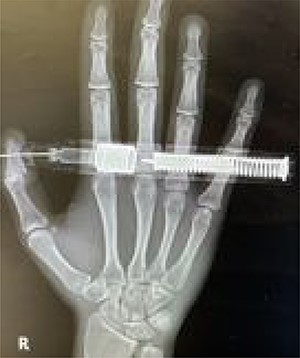

The patient remained under observation for a couple of hours. He was discharged after his condition remained stable with normal vascular findings. He was instructed to visit the ED if his condition worsened or if any signs of vascular compromise occurred. He was also educated on the proper handling and administration of the epinephrine autoinjector. He was discharged on prophylactic antibiotic and analgesia. On his follow-up visit 7 days after the accident, the puncture would have healed and vascularity and sensation were intact (Fig. 4).

On follow-up, 7 days after the accident. The wound had healed completely.